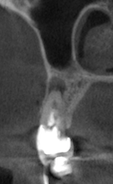

Santi Опубликовано 31 октября, 2023 Поделиться Опубликовано 31 октября, 2023 (изменено) Короткая нарезка с операции резекции 14-15. Апикально материал на основе минерал триоксид агрегата. Критике и комментам всегда рад. Изменено 31 октября, 2023 пользователем Santi 5 2 Ссылка на комментарий